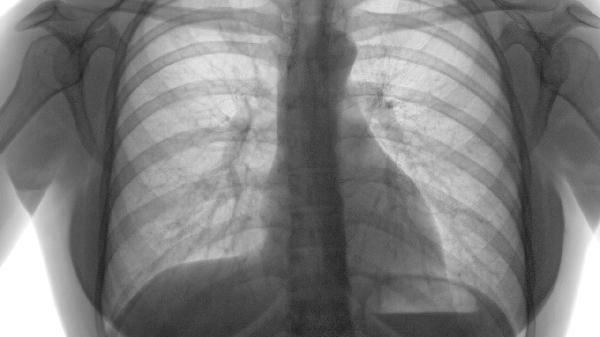

CT显示肺气肿病变范围超过30%时属中重度,可能伴随低氧血症。这类患者需要长期氧疗,使用糖皮质激素如布地奈德联合长效支气管扩张剂如福莫特罗进行维持治疗。严重者可出现肺大疱,需评估是否需行肺减容手术。